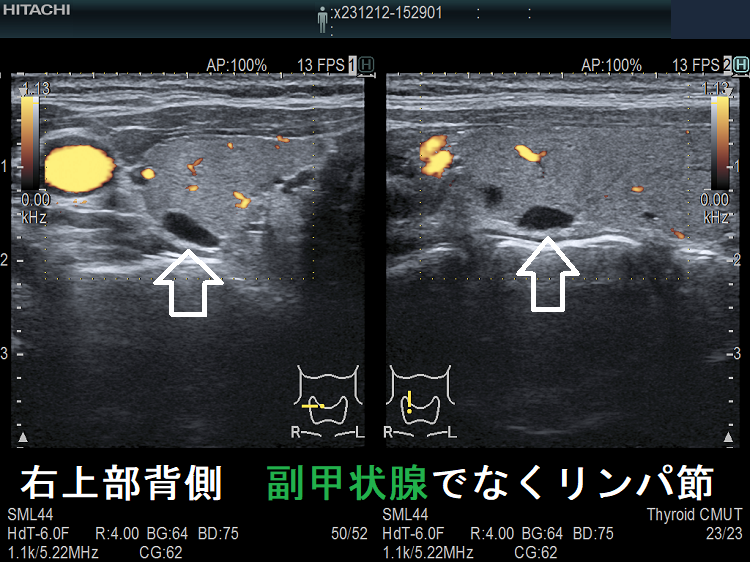

(➸)原因となる副甲状腺腺腫、副甲状腺癌、副甲状腺過形成をデジタルハイビジョン超音波診断装置で診断。エコーでは、甲状腺とのインピーダンスの違いにより、甲状腺-副甲状腺境界部に線状高エコーが生じます(右図の↓)。内部は中心血流を認め、リンパ節でないのが分かります。

副甲状腺腺腫のように見えるも、実はただのリンパ節

副甲状腺腺腫との違いとして、リンパ節では

- 内部血流が無く

- リンパ門が存在します(ここだけ血流があります)